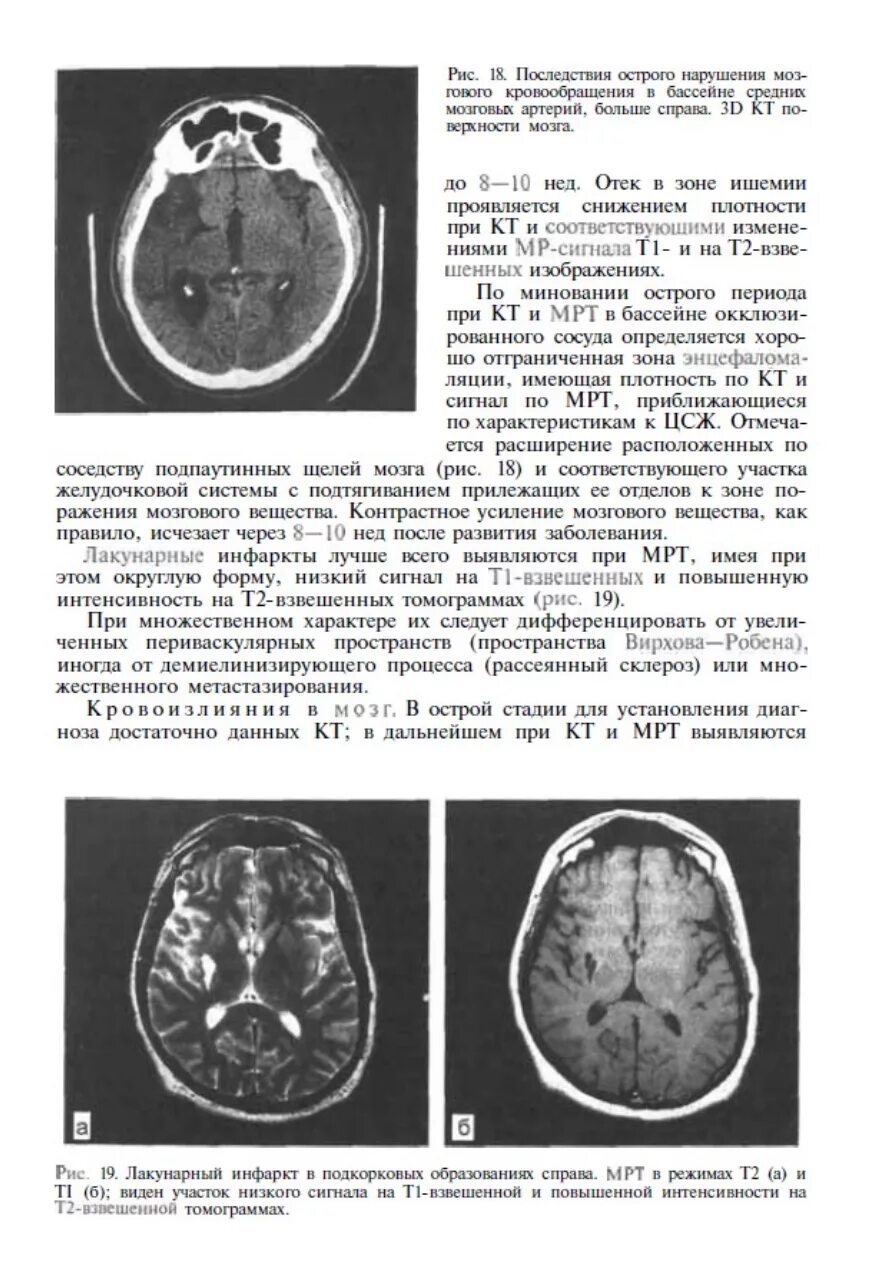

Онмк в бассейне сма